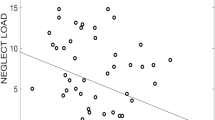

Left ACC

The calculation of variable importance revealed that abuse severity at age 16 had the highest importance for left ACC volume: VI = 5.36 (puncorr = 0.005, pFDR-corr = 0.093, see Fig. 4). Other important predictor variables were neglect severity at ages 3 (VI = 2.8, puncorr = 0.016, pFDR-corr = 0.197) and 4 (VI = 4.85, puncorr = 0.004, pFDR-corr = 0.093). Sex revealed no predictive importance (VI = 0.21, puncorr = 0.12). In a correlation analysis, neglect at ages 3 and 4 years showed a significant positive association with the volume of the left ACC. For abuse severity at age 16, a significant association with the volume of the left ACC could not be found in a correlation analysis.

Since Herzog et al. used the same correction for cranial volume and age, mainly results of the Mannheim-version are shown. Only sensitive periods of abuse have been tested in two versions. The left ACC showed a correlation with timing-specific severity of neglect at ages 3 and 4 (ages 3: r = 0.233, p = 0.039, and ages 4: r = 0.282, p = 0.012) in the female cohort (see Table 4).

Our findings indicate maltreatment-dependent ACC volume alterations. The results suggest that the main type-specific timing of CM has an impact on left ACC volume, with neglect in early childhood and abuse in adolescence having the greatest impact. We discovered that there was a positive association between the timing-specific effects of neglect and left ACC volume. These results confirm the sensitive period of the ACC to neglect previously identified by Herzog, et al.34